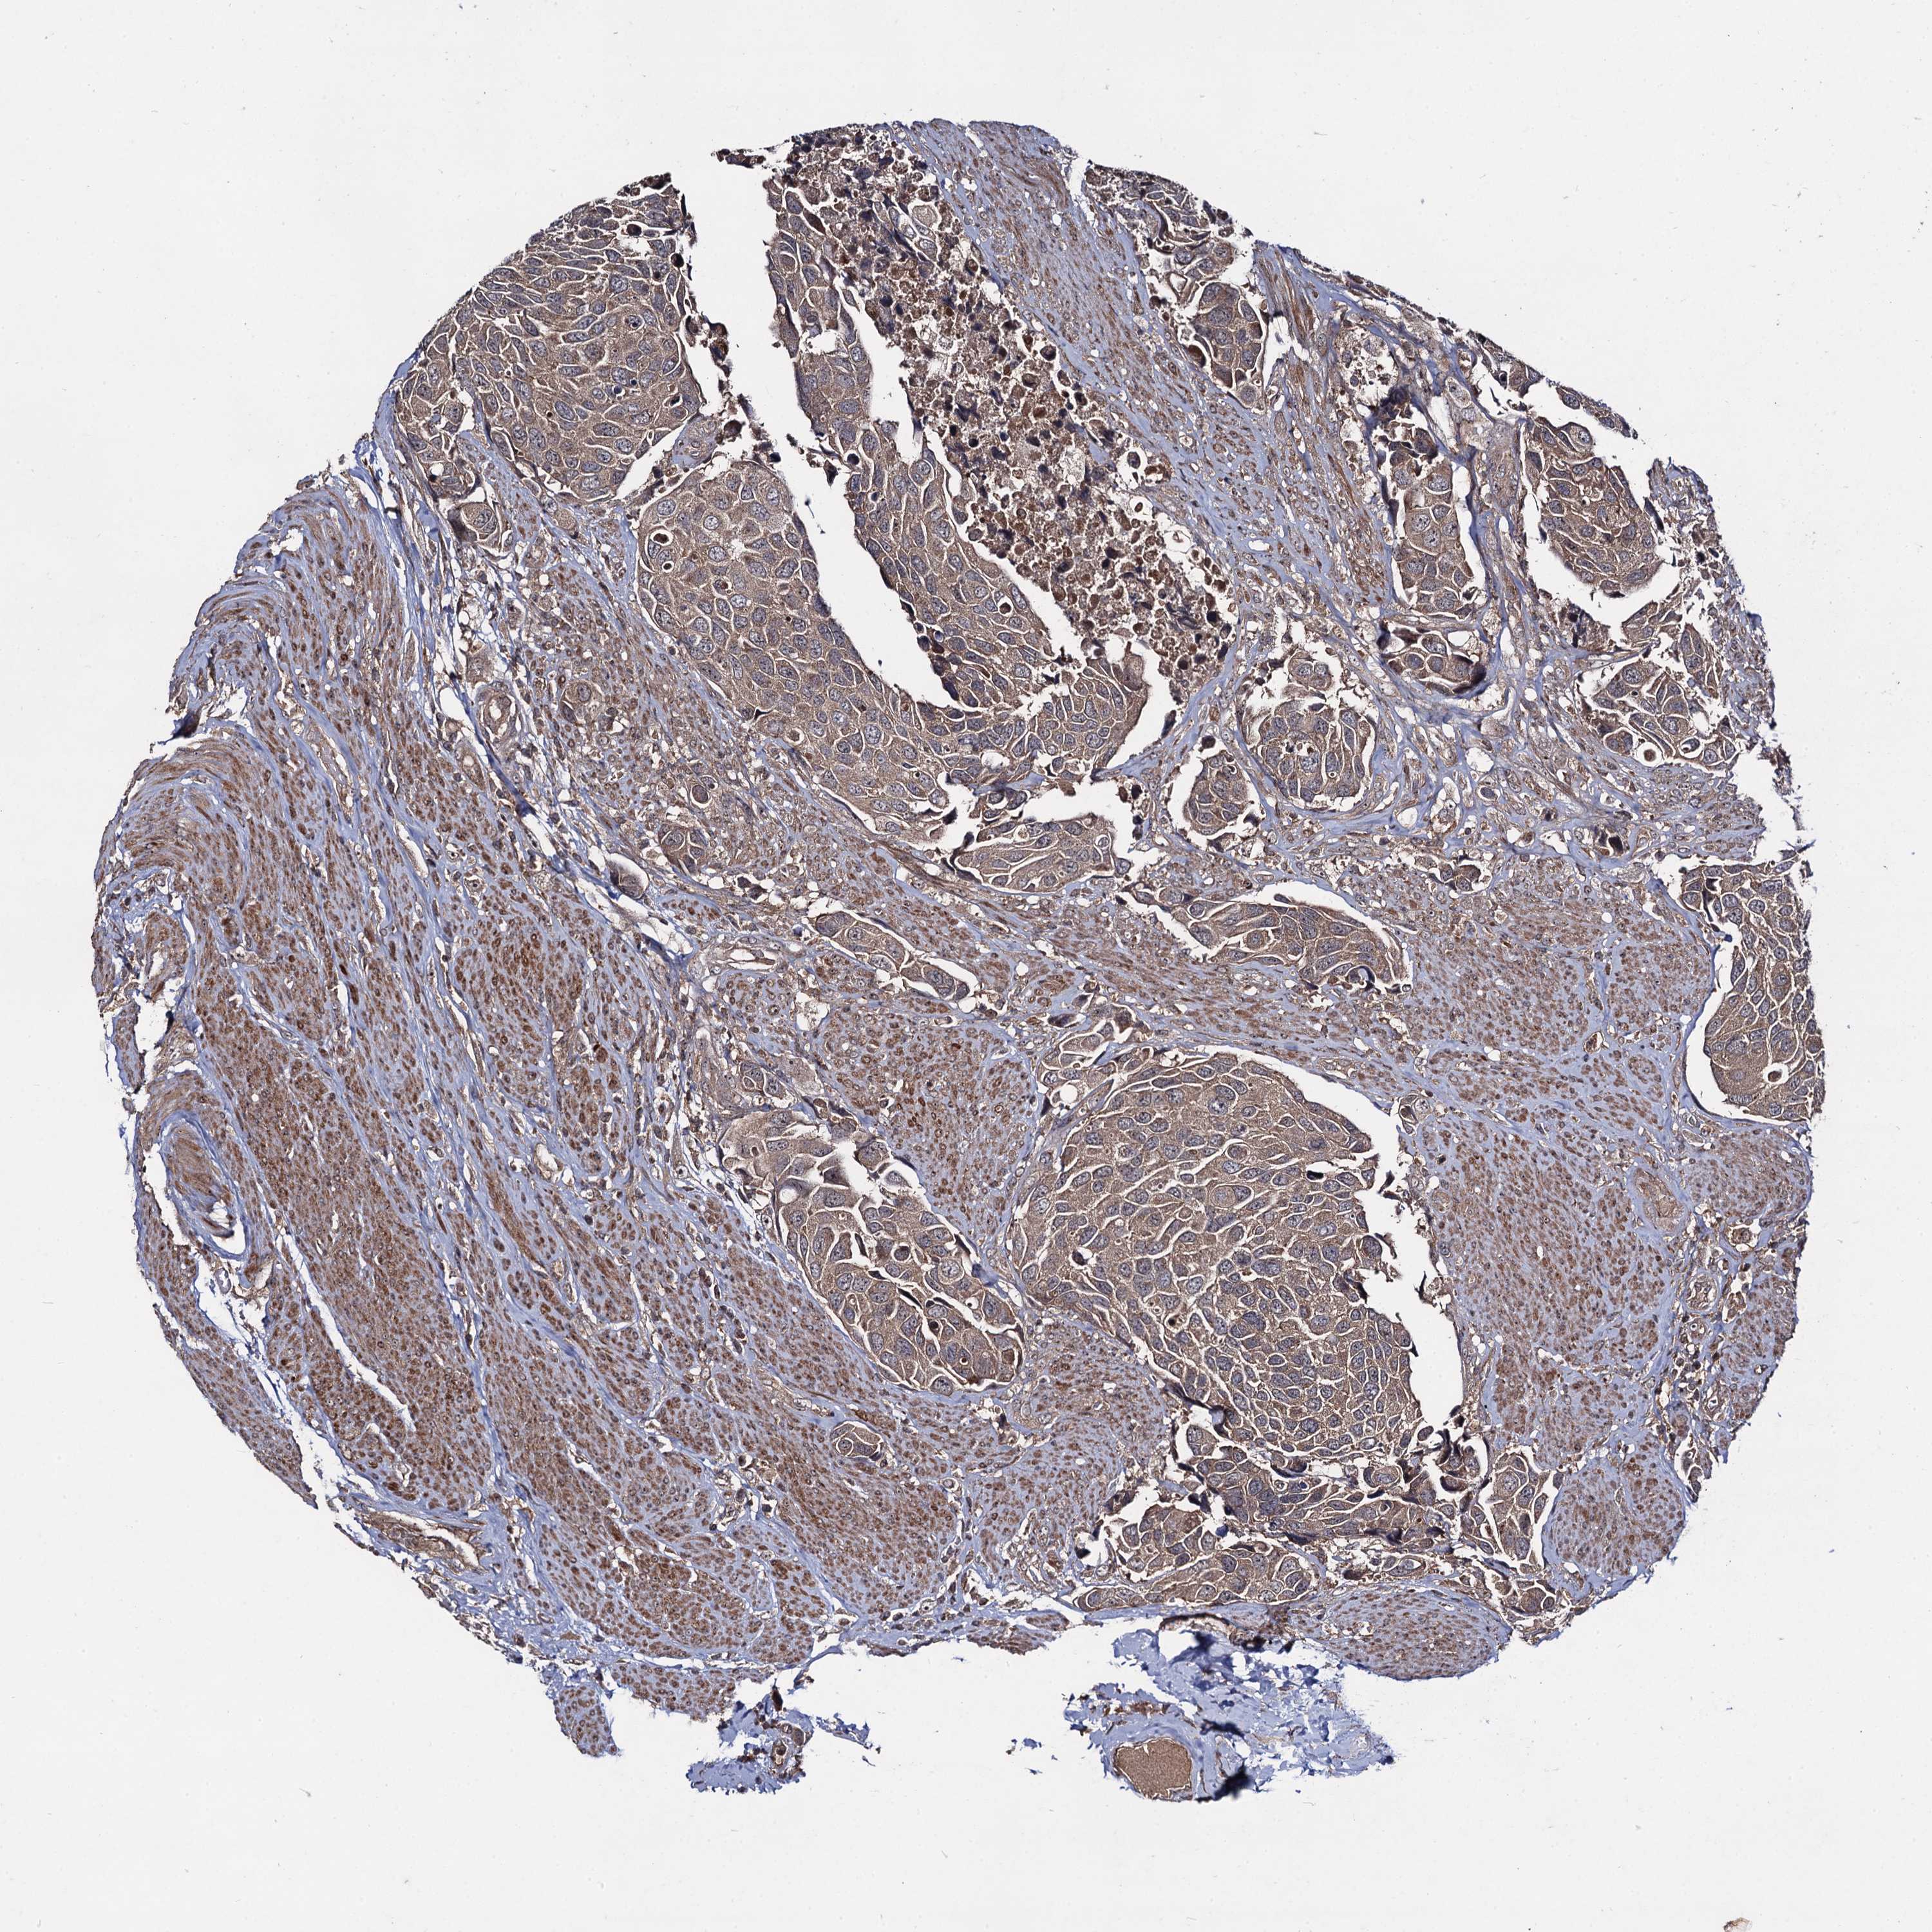

UROTHELIAL CANCER - Protein expressioni

A mouse-over function shows sample information and annotation data. Click on an image to view it in a full screen mode. Samples can be filtered based on level of antibody staining by selecting one or several of the following categories: high, medium, low and not detected. The assay and annotation is described here.

Note that samples used for immunohistochemistry by the Human Protein Atlas do not correspond to samples in the TCGA dataset.

Antibody stainingi

Antibody staining in the annotated cell types in the current human tissue is reported as not detected, low, medium, or high, based on conventional immunohistochemistry profiling in selected tissues. This score is based on the combination of the staining intensity and fraction of stained cells.

Each image is clickable and will lead to virtual microscopy that enables deeper exploration of all samples and also displays staining intensity scores, fraction scores and subcellular localization as well as patient and tissue information for each sample.

Antibody HPA041507

Antibody HPA041599

Staining

High

Medium

Low

Not detected

Intensity

Strong

Moderate

Weak

Negative

Quantity

>75%

75%-25%

<25%

None

Location

Nuclear

Cytoplasmic/membranous

Cytoplasmic/membranous,nuclear

Urothelial carcinoma, High grade

Urothelial carcinoma, Low grade

Urothelial carcinoma, NOS